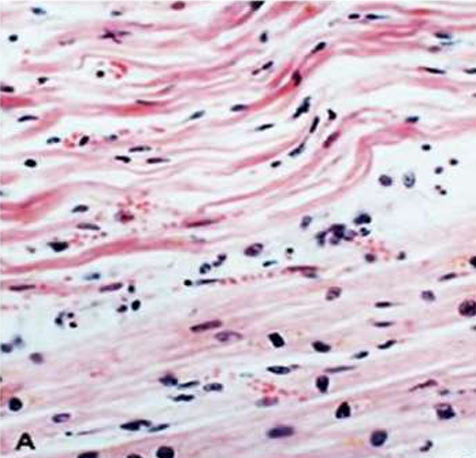

IHD: Myocardial infarction

Acute Myocardial Infarction

After 8 wks: Healed MI with replacement of the necrotic fibers by dense collagenous scar. Residual cardiac muscle cells are present